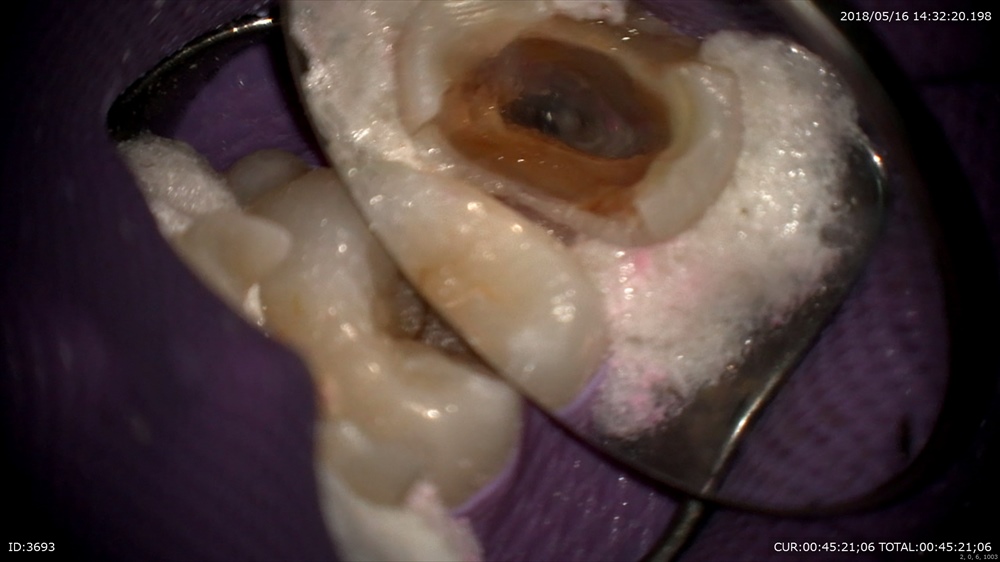

最後のケースは右上の根管治療。これもセカンドオピニオン。他院で勝手に神経を取られた。

綿が入っていて取れない。

格闘中

感染残ってる

徹底的に

OK

あれ?

2根

25倍で観察

マイクロスコープあって良かった!!